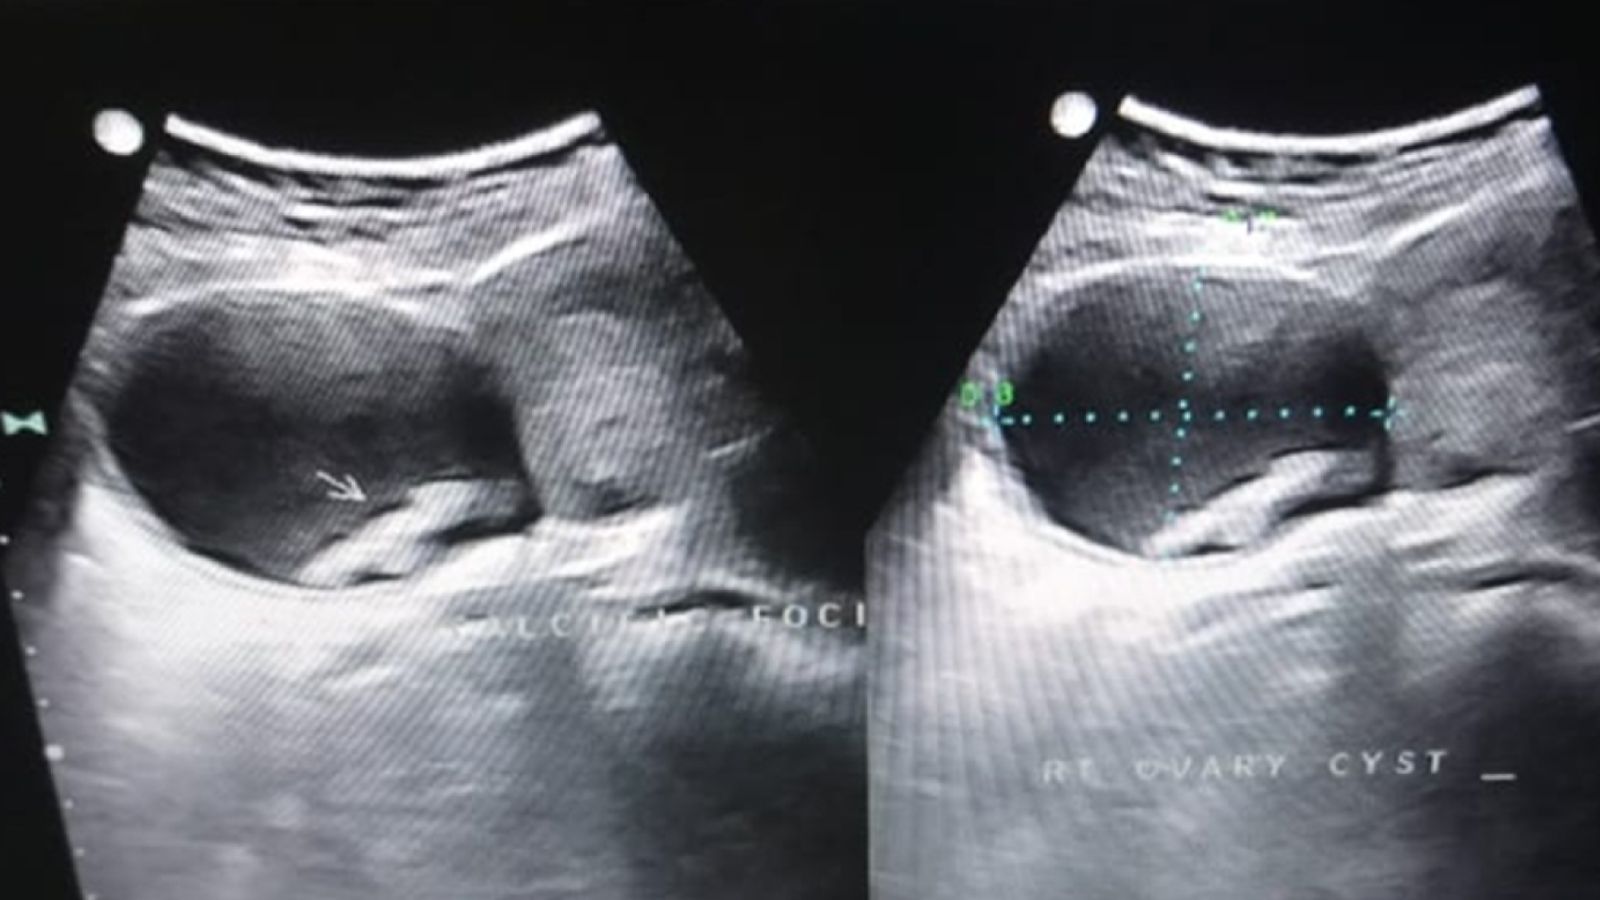

تخمدانها دو عضو کوچک بادامیشکل در دو طرف رحم هستند که وظیفه تولید تخمک و هورمونهای زنانه را بر عهده دارند. کیست تخمدان (Ovarian Cyst) به زبان ساده، کیسهای پر از مایع است که در داخل یا روی سطح یکی از این تخمدانها ایجاد میشود. این کیسهها به طرز شگفتانگیزی رایج هستند، بهخصوص در زنانی که هنوز علائم یائسگی ندارند. اغلب افراد حتی متوجه وجود آنها نمیشوند، زیرا بیشتر این کیستها کوچک، بدون علامت و کاملاً بیخطر هستند و معمولاً ظرف چند ماه خودبهخود از بین میروند.

زنان دو تخمدان دارند، یکی در سمت چپ و دیگری در سمت راست رحم. کیست میتواند روی هر یک از آنها یا گاهی روی هر دو ایجاد شود. وجود کیست تخمدان چپ به خودی خود هیچ ویژگی منحصربهفردی ندارد. ماهیت، خطر و درمان آن دقیقاً مانند کیست راست است و فقط به نوع، اندازه و علائم آن بستگی دارد، نه به موقعیتش. به طور مشابه، کیست تخمدان راست نیز بر اساس موقعیتش طبقهبندی خطرناکی ندارد. یک کیست تخمدان در سمت راست میتواند به همان اندازه بیخطر (یا در صورت عوارض، خطرناک) باشد که در سمت چپ است.

آیا کیست تخمدان چپ خطرناک است یا راست؟ پاسخ علمی کوتاه «خیر» است. هیچ مدرک پزشکی وجود ندارد که نشان دهد کیستهای یک طرف ذاتاً خطرناکتر از طرف دیگر هستند.